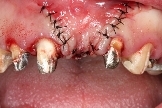

右側前牙進行牙冠增長術,調整牙齒比例。

左側側門牙進行牙肉增生手術,解決牙齦萎縮問題。